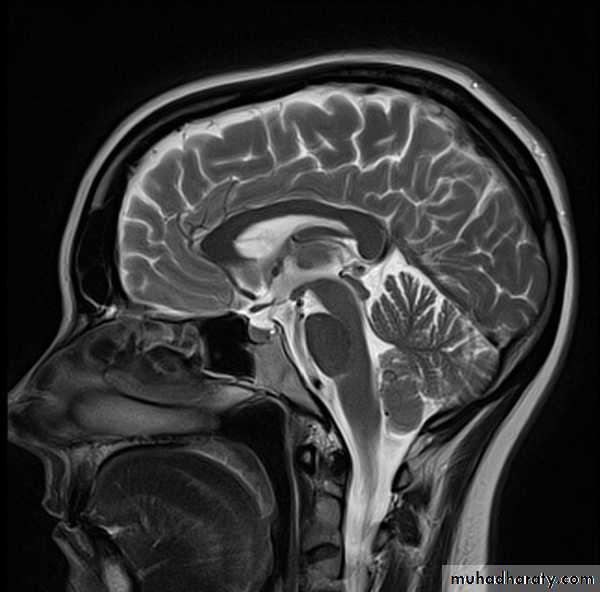

• MRI uses the magnetic properties of spinning hydrogen atoms to produce images.

• Large powerful magnet: Most current medical MRI machines have field strengths of 1.5 or 3.0 tesla. The hydrogen atoms within the patient align in a direction either parallel or antiparallel to the strong external field. A greater proportion aligns in the parallel direction so that the net vector of their alignment, and therefore the net magnetic vector, will be in the direction of the external field. This is known as longitudinal magnetization.

• A second magnetic field is applied at right angles to the original external field. This second magnetic field is known as the radiofrequency pulse (RF pulse), because it is applied at a frequency in the same part of the electromagnetic spectrum as radio waves. A magnetic coil, known as the RF coil, applies the RF pulse. The RF pulse causes the net magnetization vector of the hydrogen atoms to turn towards the transverse planeThe component of the net magnetization vector in the transverse plane induces an electrical current in the RF coil. This current is known as the MR signal.

Applications of MRI:

• Imaging modality of choice for most brain and spine disorders• Musculoskeletal disorders, including internal derangements of joints and staging of musculoskeletal tumors

Particular advantages of MRI include:

• Excellent soft tissue contrast and characterization

• Lack of artefact from adjacent bones, e.g. pituitary fossa

• Multiplanar capabilities

• Lack of ionizing radiation.